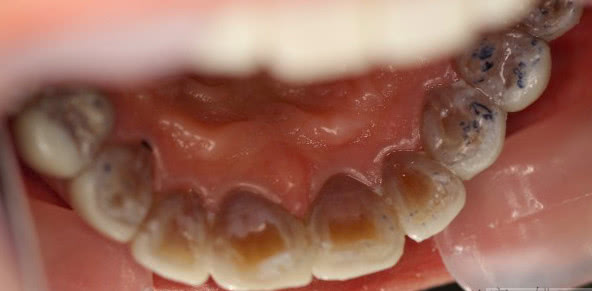

四环素牙就是因四环素药物造成的四环素沉积于牙,造成牙釉质发育不良,造成牙齿成黄色牙。

多是孕妇在怀孕期间或者婴儿误食含有四环素药物,致使婴儿长大牙齿成四环素牙。如下图所示。